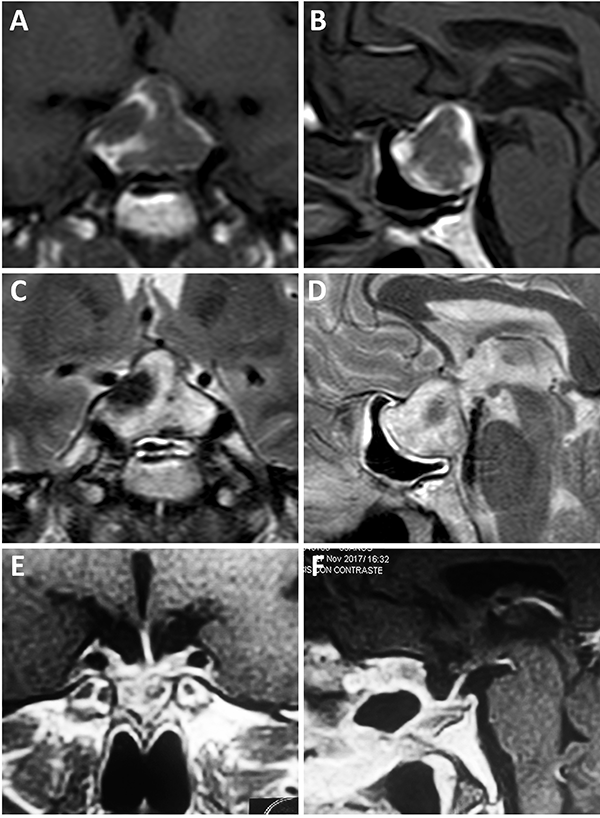

Un factor interesante de este novedoso concepto es que el tipo de barrera puede evidenciarse en la RM preoperatoria. De este modo, existen 3 subtipos de barrera selar según la radiología:

Los pacientes con una barrera débil tienen mayor riesgo de fístula intraoperatoria de LCR. La barrera fuerte es un factor protector de fístula de LCR.11,60

Figura 6: Barrera selar fuerte. A-B) RM preoperatoria. C-D) Hallazgos intraquirúrgicos. E-F) RM postoperatoria. Flechas amarillas: interlinea > 1mm. Tomado de Campero A, Villalonga JF, Basso A. Anatomical risk factors for intraoperative cerebrospinal fluid leaks during transsphenoidal surgery for pituitary adenomas. World Neurosurg. 2019;124:346-55.

Figura 7: Barrera selar mixta. A y C) RM preoperatoria corte coronal; B y D) RM preoperatoria corte sagital; E-F) Hallazgos intraoperatorios; G-H) RM postoperatoria. Flechas y líneas: color rojo indican barrera débil; color amarillo indican barrera fuerte. Tomado deVillalonga JF, Ries-Centeno T, Sáenz A, Solari D, Cervio A, Campero A. The mixed sellar barrier: a new subtype of this novel concept. World Neurosurg. 2019;132:5-13.

Figura 8: Barrera selar débil. A-B) RM preoperatoria; C-D) Hallazgos intraoperatorios. E-F) RM postoperatoria. Flechas rojas: interlínea < 1mm. Tomado de Campero A, Villalonga JF, Basso A. Anatomical risk factors for intraoperative cerebrospinal fluid leaks during transsphenoidal surgery for pituitary adenomas. World Neurosurg. 2019;124:346-55.